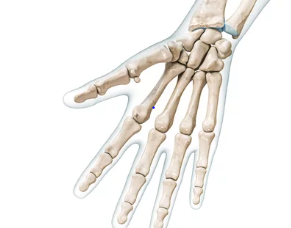

손가락 관절은 우리 몸에서 미세한 움직임을 담당하는 중요한 부분입니다. 일상생활에서 반복적인 작업, 부적절한 자세, 또는 외상 등으로 인해 관절에 무리가 가게 되면 다양한 전조증상이 나타날 수 있습니다. 이러한 증상들은 통증, 부기, 뻣뻣함 또는 움직임의 제한과 같은 형태로 나타나며, 이는 관절염이나 힘줄의 문제를 예고하는 신호일 수 있습니다. 이 글에서는 손가락 관절의 전조증상을 인지하는 방법과 초기 대응 치료방법에 대해 알아보고, 장기적인 관리와 예방책에 대해서도 논의할 것입니다. 건강한 손가락 관절을 유지하기 위한 첫걸음은 증상을 조기에 발견하고 적절한 조치를 취하는 것에서 시작됩니다. 오늘은 손가락염 관절 전조증상 및 치료방법 알아보기에 대해 알려드리겠습니다.

손가락 관절염은 일상생활에 불편함을 주는 흔한 질환으로, 초기에 적절한 치료를 받지 않으면 만성적인 통증과 기능 장애를 초래할 수 있습니다. 이 질환의 전조 증상으로는 손가락의 뻣뻣함, 붓기, 관절 부위의 압통 등이 있으며, 이러한 증상들은 보통 아침에 더욱 심해집니다. 조기 진단과 함께 통합적인 치료 접근 방식을 통해 손가락 관절염의 진행을 늦추고 증상을 완화할 수 있습니다.

손가락 관절은 우리 몸에서 매우 중요한 역할을 합니다. 일상생활에서 다양한 활동을 가능하게 하는 이 관절들은 때때로 다양한 증상을 경험할 수 있습니다. 손가락 관절 증상은 단순한 불편함에서부터 심각한 건강 문제에 이르기까지 다양합니다.